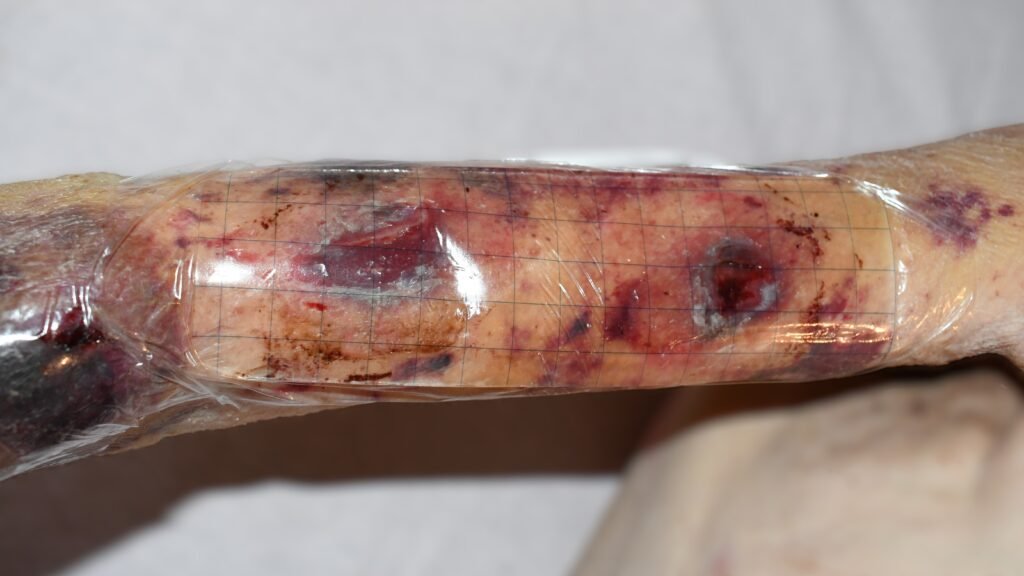

Wundauflagen zur Nasstherapie

Zusätzliche – Fotos ![]() 1 Videos

1 Videos ![]() 2

2